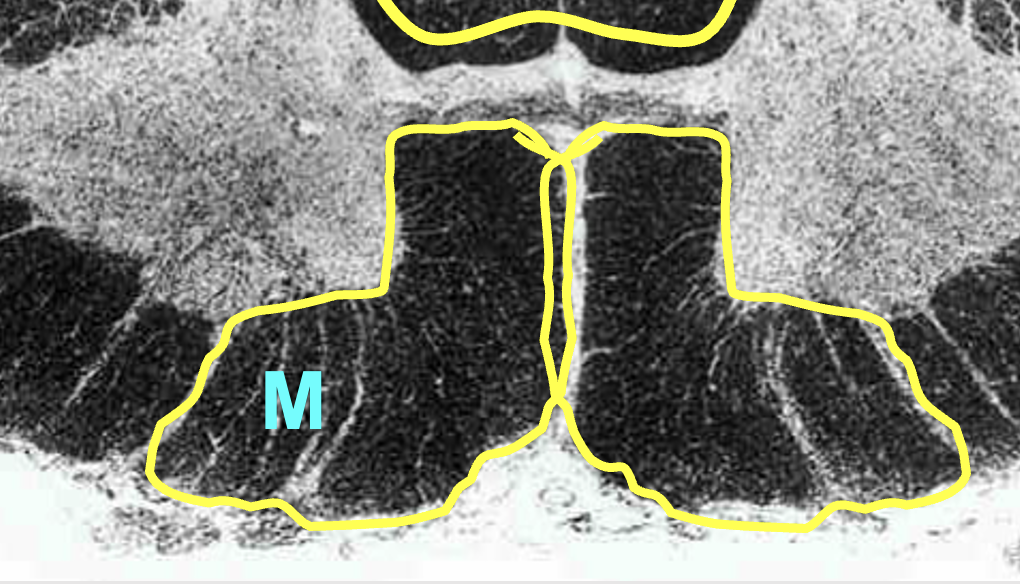

ventral horn

ventral rootlets

ventral root

carry motor information from the CNS to the periphery

butterfly

center of the spinal cord; contains neurons and glia (grey matter)

grey matter

primarily made up of neurons (cell bodies)

ventral column/funiculus

white matter located between two ventral horns; contain multiple tracts

motor informsation (descending)